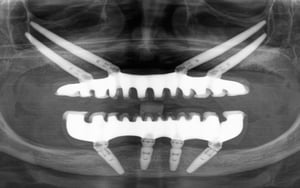

Uz pomoć naprednih kirurških tehnika i posebnih zigomatičnih, pterigoidnih, transnazalnih, subnazalnih i transsinusnih implantata, IMED Full Arch Concept® omogućuje fiksno protetsko rješenje čak i za slučajeve s potpunim gubitkom kosti čeljusti.

Koristimo posebne zygoma, pterigoidne, transsinusne i transnazalne implantate koji se sidre u čvrste koštane strukture izvan zubnog grebena. Tako je moguće ugraditi fiksni most čak i kod izrazito resorbiranog grebena, bez klasične nadogradnje kosti.

IMED Full Arch Concept® temelji se na digitalnim CBCT snimkama, intraoralnom skeniranju i CAD/CAM tehnologiji. To omogućuje precizno planiranje položaja implantata i izradu mosta koji je prilagođen vašem licu, zagrizu i osmijehu.

Sam zahvat traje otprilike 2 do 3 sata i izvodi se pod općom (potpunom) anestezijom, pa je za pacijenta u potpunosti bezbolan. Iskusni tim specijalista oralne kirurgije, subspecijaliziran za najteže implantološke operacije, prema digitalnom planu postavlja odabrane implantate u čvrste koštane strukture kako bi osigurali maksimalnu stabilnost.